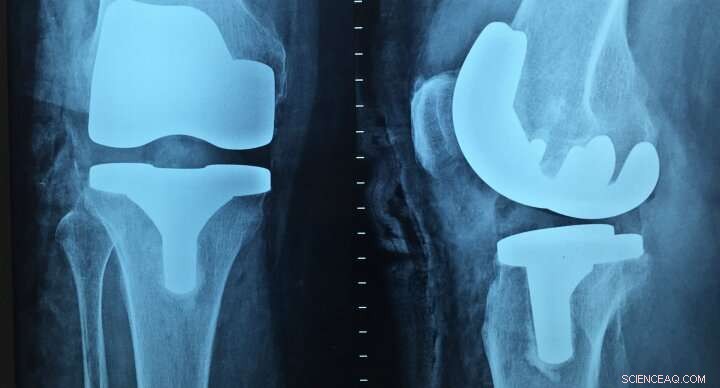

A new thermoplastic biomaterial, which is tough and strong but also easy to process and shape has been developed by researchers at the University of Birmingham.

A type of nylon, the material's shape memory properties enable it to be stretched and molded but able to reform into its original shape when heated. This makes it useful for medical devices such as bone replacements, where minimally invasive surgery techniques require additional flexibility in implant materials.

Senior researcher, Professor Andrew Dove, says: "This material offers some really distinctive advantages over existing products used to manufacture medical devices such as bone and joint replacements. We think it could offer a cost-effective, versatile and robust alternative in the medical device marketplace."